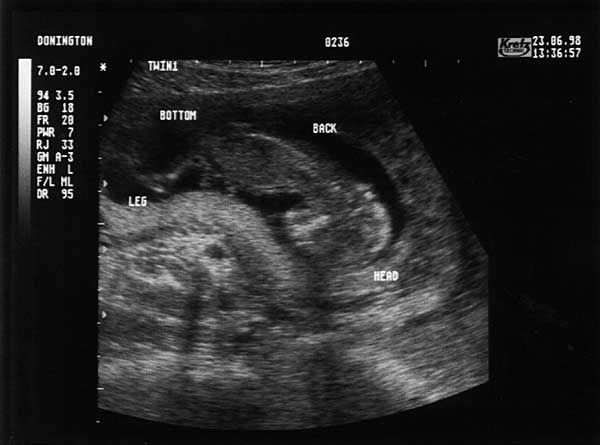

13 Weeks - Tuesday 23rd June 1998 (Approx 75mm)

Thirteen Week Scan 2

Twin 1 (Emma), section through body, leg top left, head middle right.